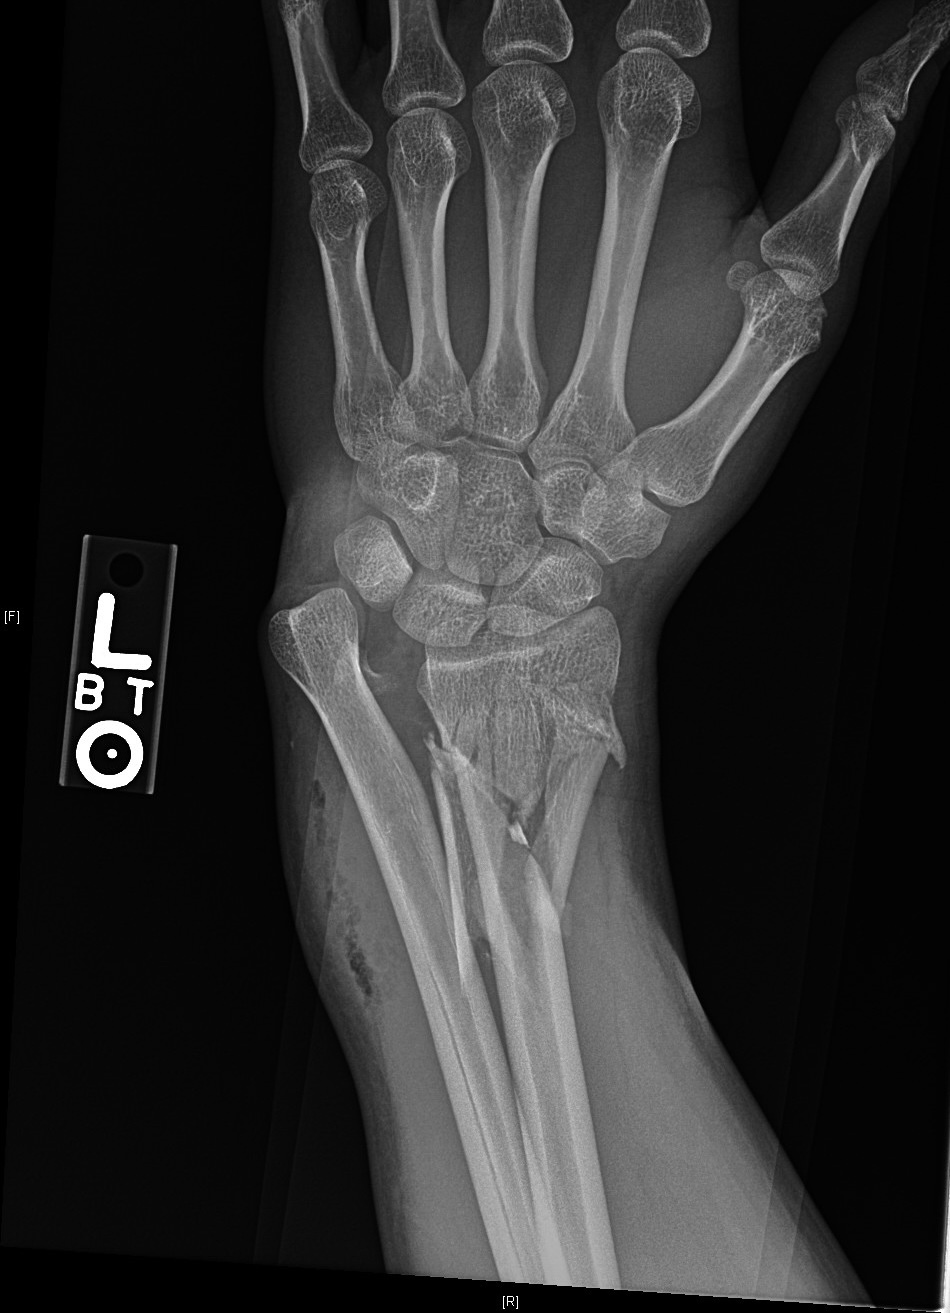

Plain radiographs revealed a severely comminuted and displaced distal left radial diaphyseal fracture and a dislocated distal left radioulnar joint fracture with adjacent subcutaneous soft tissue emphysema [Figure 1].

There were no fractures or dislocations involving the remainder of the left ulna and radius. A hematoma block was performed in the ED and the wrist was splinted to provide some immobilization [Figure 2]. The patient also received prophylactic intravenous cefazolin, and tetanus immunoglobulin.